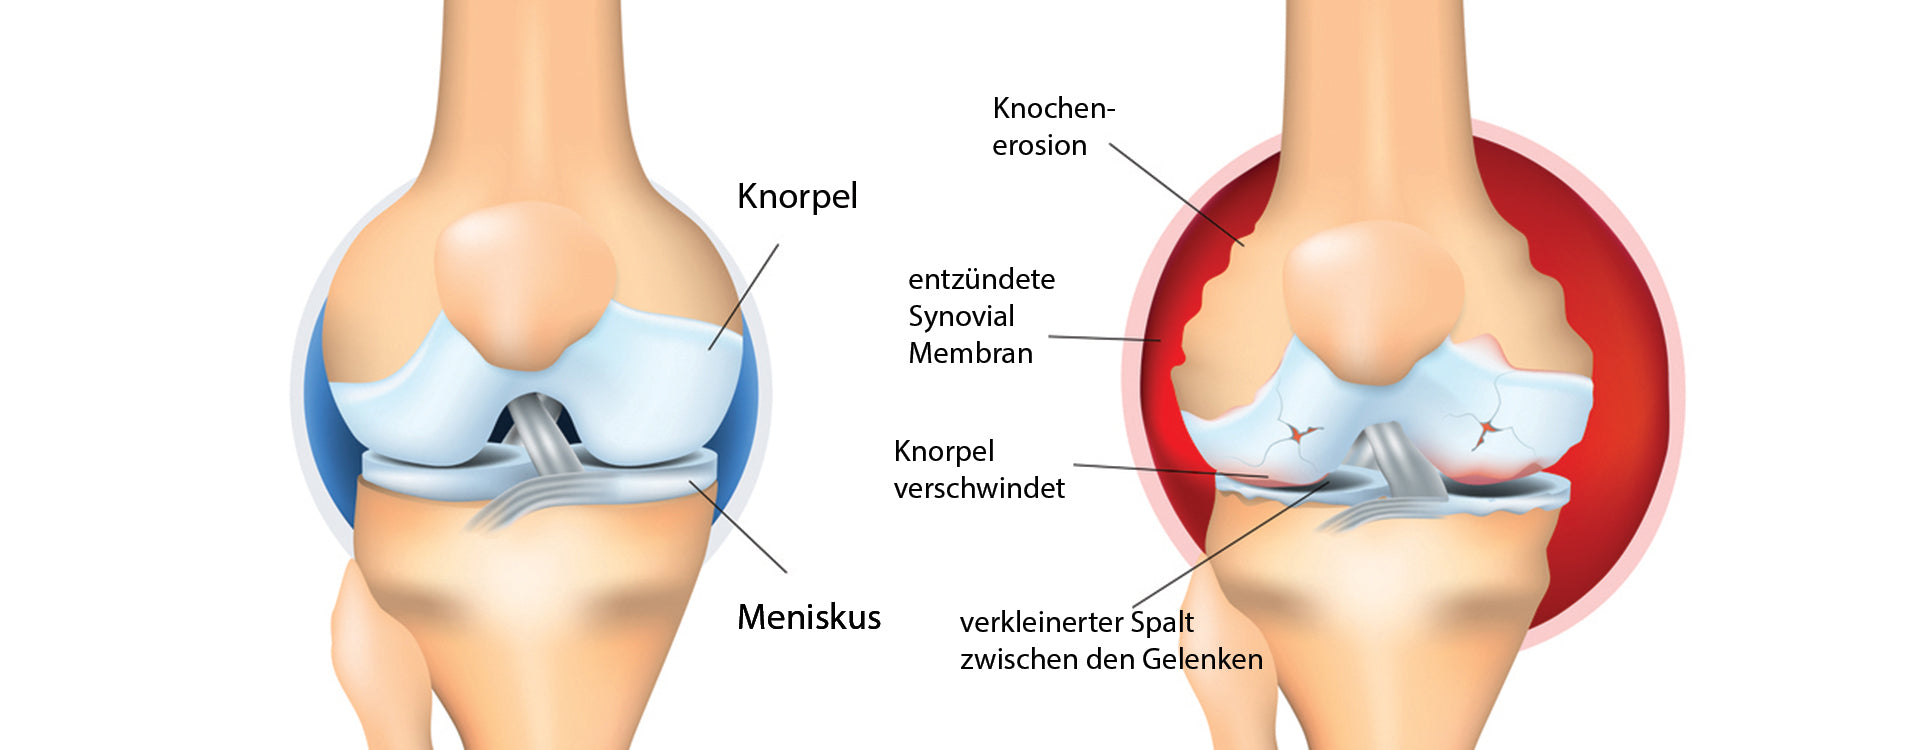

Damit die Gelenkknochen bei Bewegung nicht aneinander reiben, sind sie von einer dünnen Schicht aus Knorpel geschützt. Diese Knorpelmatrix kann Wasser speichern und wirkt dadurch wie ein Stoßdämpfer, der den Druck abfedert. Knorpel besteht aus wichtigen Bestandteilen wie Glucosaminsulfat, Chondroitinsulfat, Hyaluronsäure und Kollagen.

Ähnlich wie man ein quietschendes Türscharnier mit Öl schmiert, gibt es im Körper eine spezielle Gelenkschmiere – die Gelenkflüssigkeit (Synovia). Da der Gelenkknorpel nicht direkt über das Blut versorgt wird, muss diese Flüssigkeit die Nährstoffe liefern. Allerdings fließt die Gelenkflüssigkeit nicht von allein; erst durch Bewegung wird sie in den Knorpel „eingearbeitet“.

Ausgewogene Ernährung beeinflusst die Gelenkgesundheit direkt: Knorpel wird über die Synovia versorgt – fehlen Nährstoffe, gerät das Gleichgewicht von Aufbau und Abbau ins Wanken.